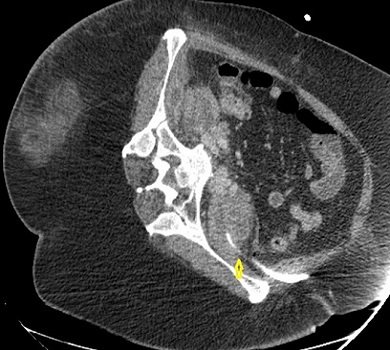

Παρακάτω φαίνονται οι παροχετεύσεις (κίτρινα βέλη) που καταλήγουν εντός των αποστηματικών κοιλοτήτων σε διάφορες τομές της αξονικής τομογραφίας.